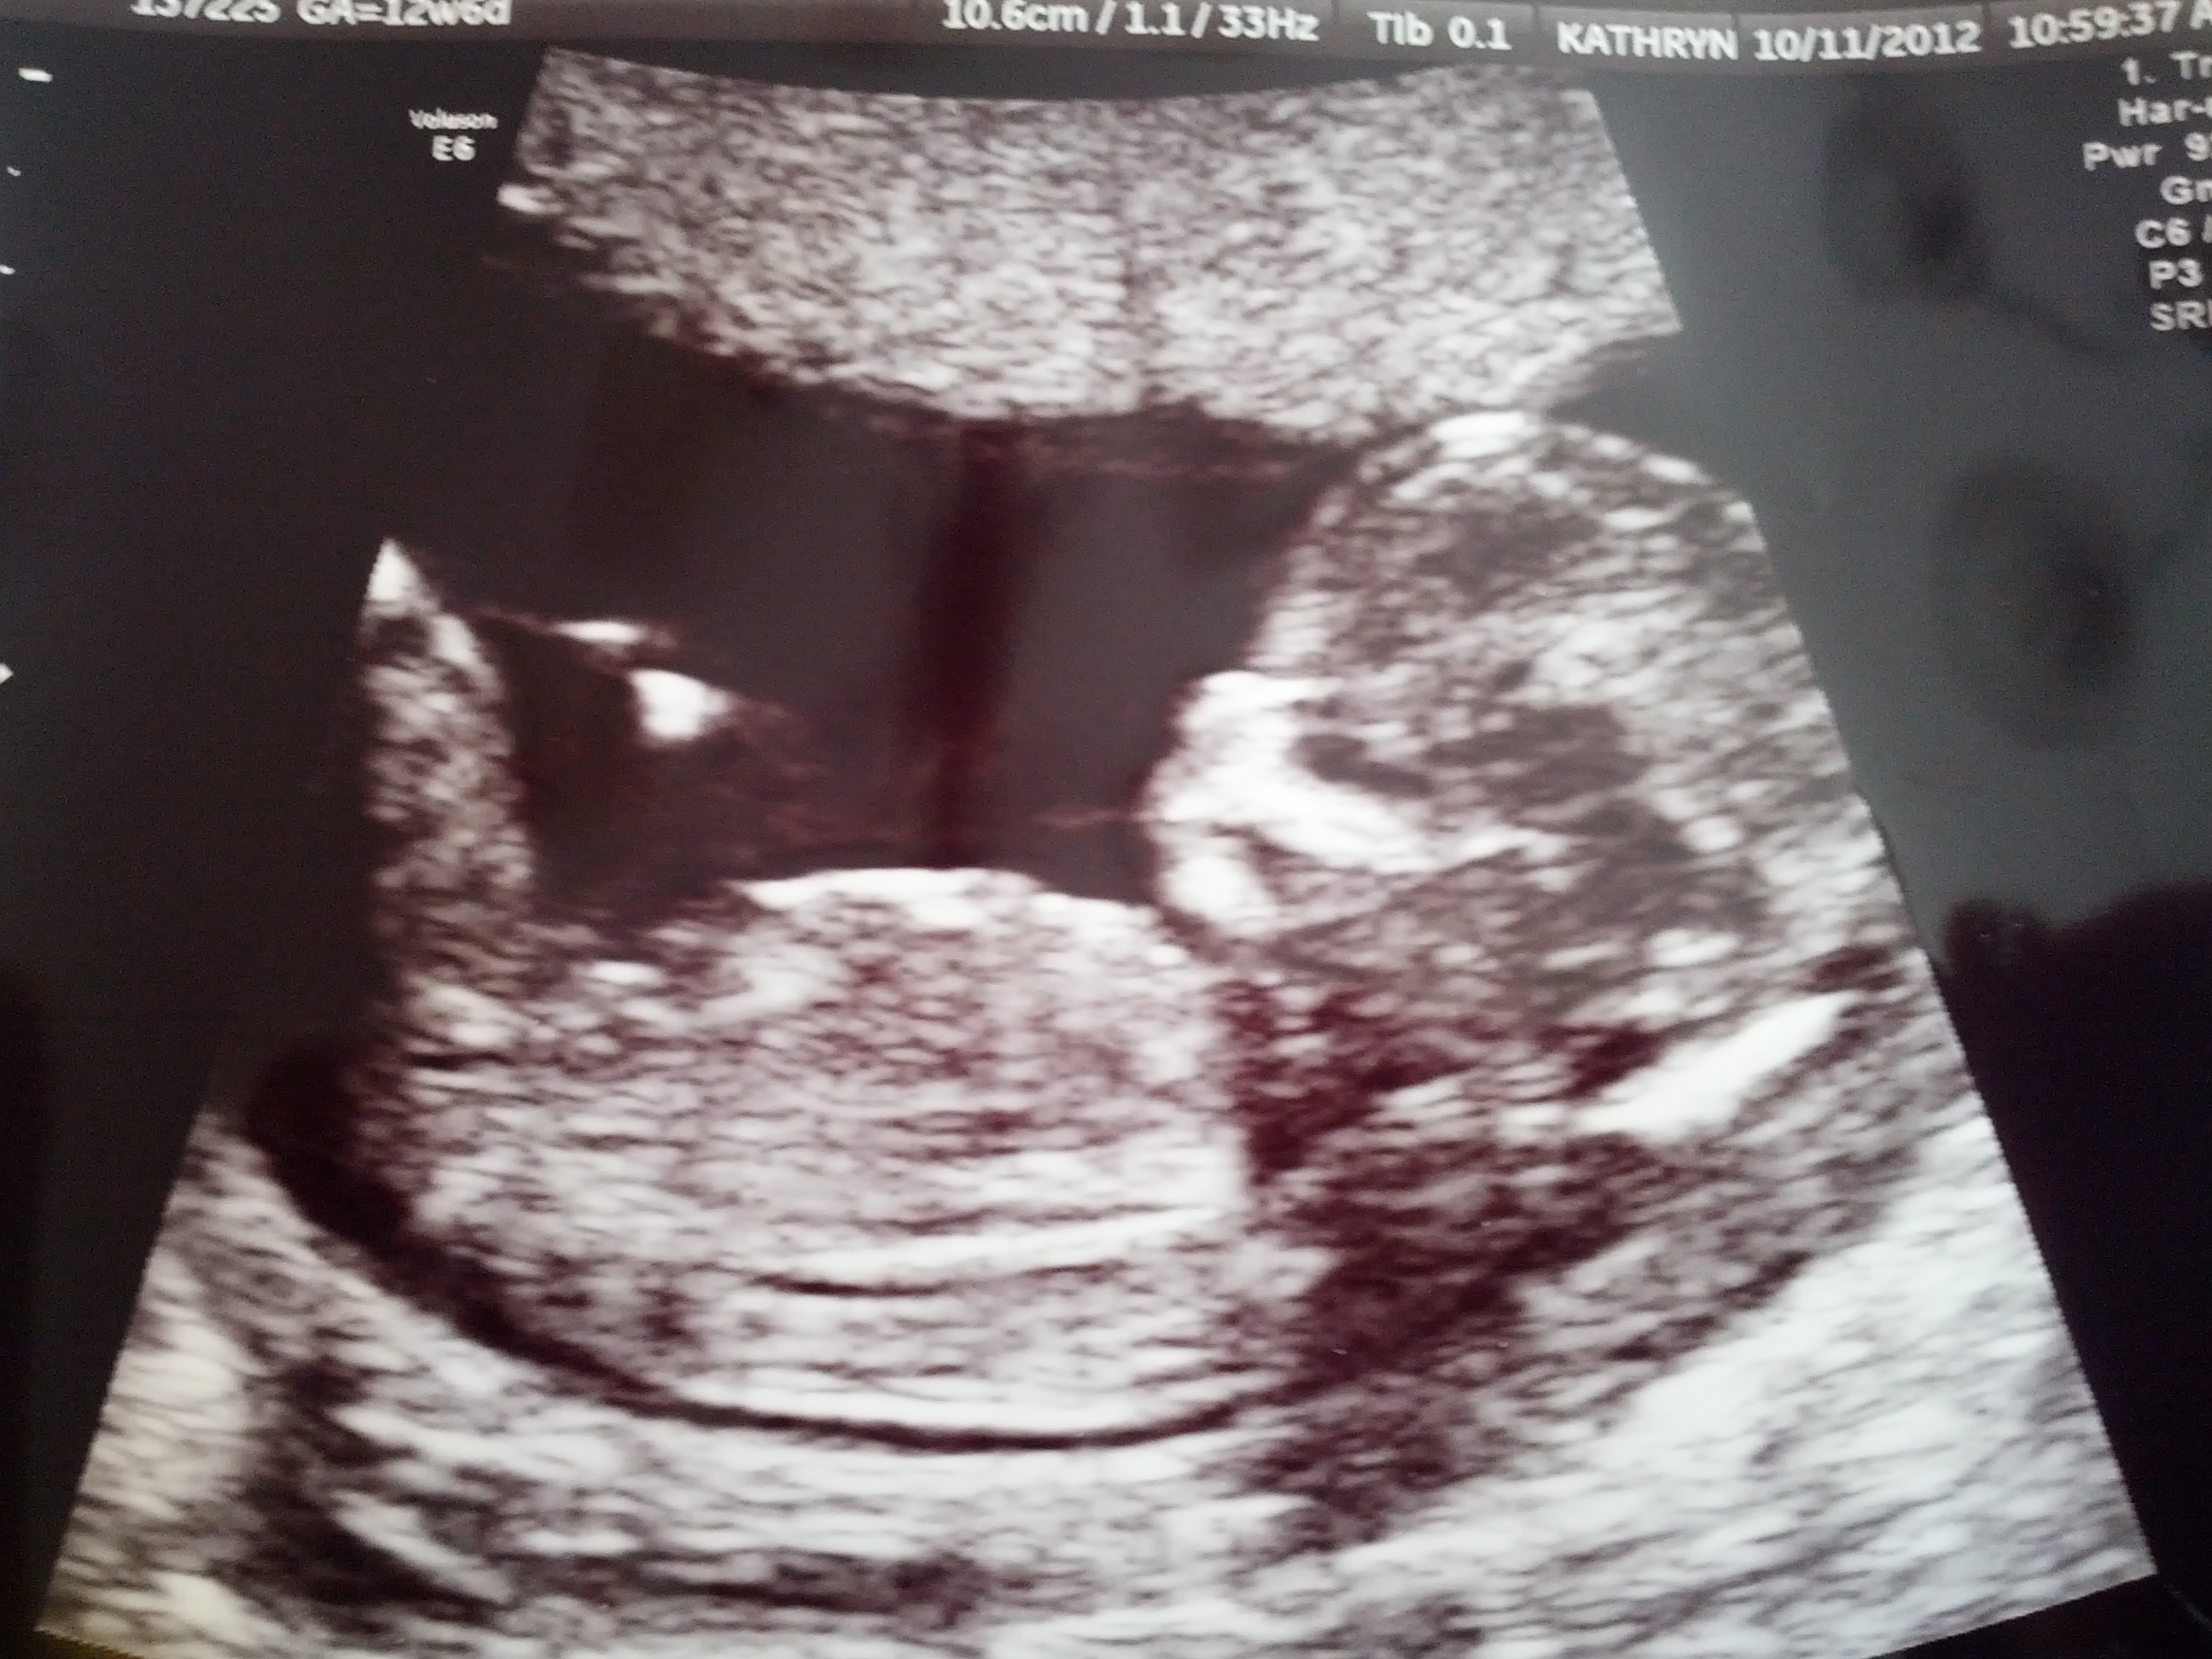

Here they are....very obvious to me and the tech. She did a potty shot and there was something between the legs that she was 50/50 on and that it wasn't as prominent as most boys she sees. Then, the nub said it all.

Attachment 5294